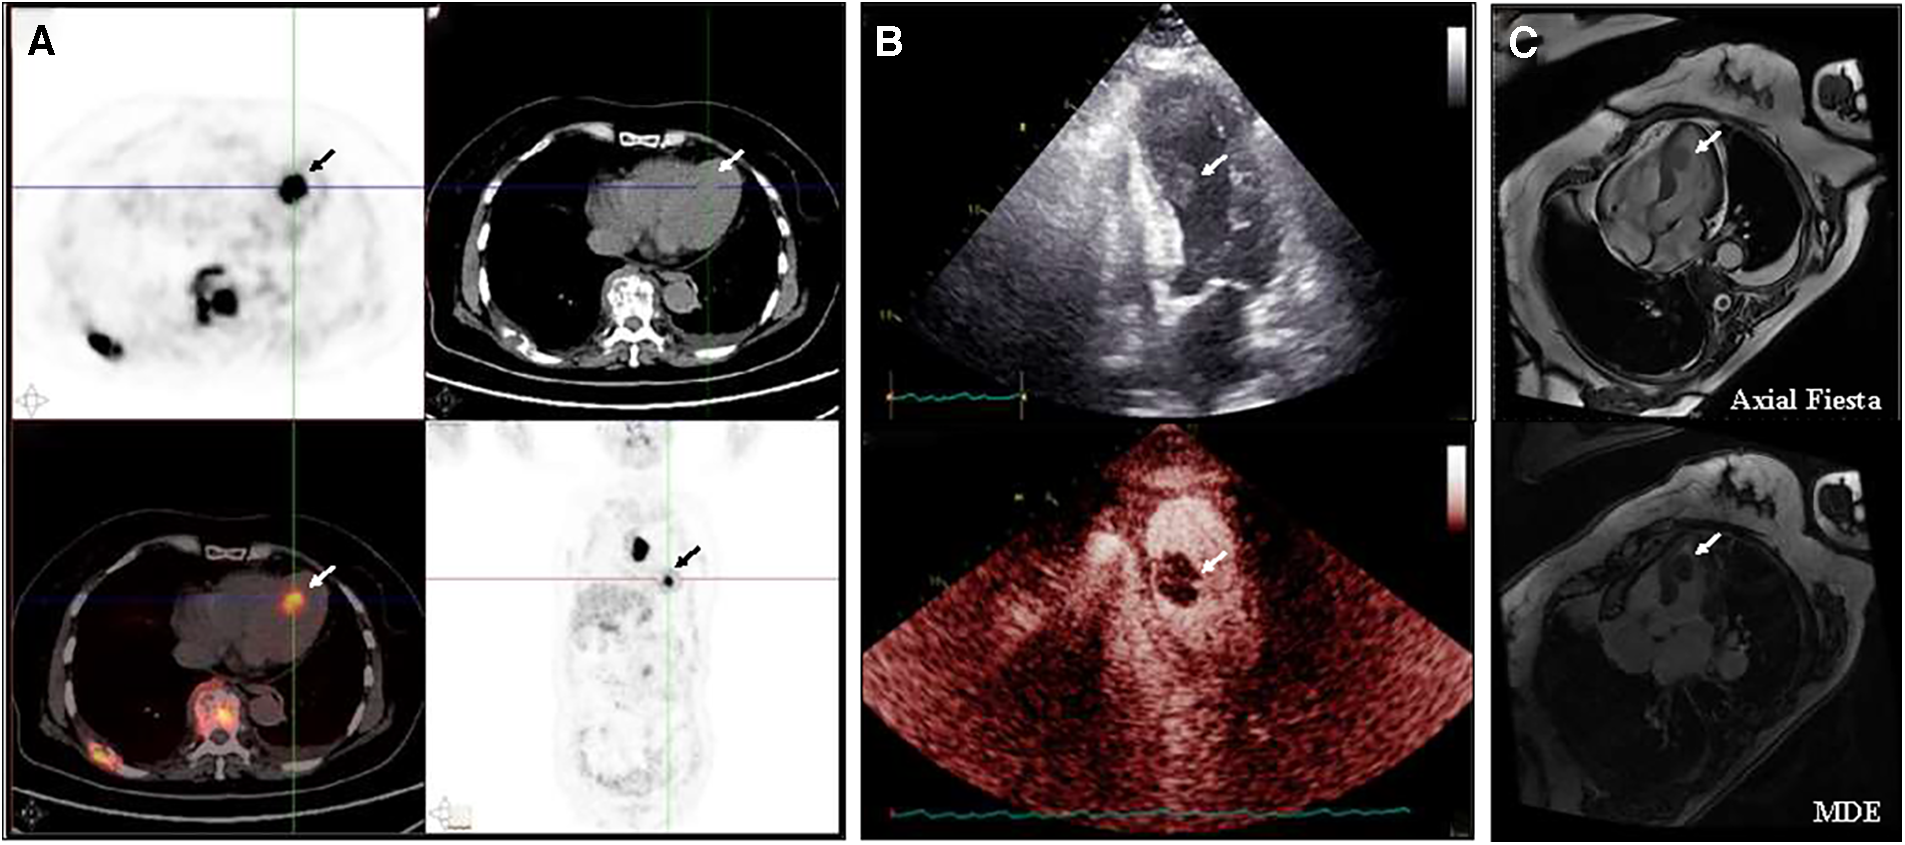

To determine whether the masses were malignant, positron emission tomography (PET) imaging was performed with . The PET imaging showed multiple masses in the left ventricle, gallbladder, right adrenal gland, and right erector spinae with multiple enlarged lymph nodes and bone destruction throughout the body, all of which had significantly increased FDG uptake. In particular, the maximum standardized uptake value for left ventricular masses was 16.5 and 19.7 after delay, consistent with malignancy (Figure 1A). Echocardiography showed a 14 × 17 mm additional echo detectable at the proximal apical segment of the septum in the left ventricle, with irregular morphology, tissue-like echoes, and mobility. Echocardiography of the cardiac chambers showed a detectable contrast-enhanced mass in the septum near the apex, with an irregular morphology, measuring approximately 12 × 22 mm, with a wide base and high mobility at the point of attachment, and with a relatively large amount of contrast filling detectable within it, which was considered to be malignant (Figure 1B). The left ventricular ejection fraction (LVEF) was 59%. Axial Fiesta of cardiac magnetic resonance (CMR) showed a mass measuring 1.6 cm × 1.1cm × 2.1 cm at the left cardiac chamber septum. Long-axis four-chamber myocardial delayed enhancement (MDE) showed nodular shadows in the left cardiac chamber, and the mass had no gadolinium enhancement (Figure 1C). The patient refused to undergo an endomyocardial biopsy because of concerns about the risks of invasive procedures. Then, the patient underwent a biopsy of the right supraclavicular lymph node.

Figure 1

Baseline imaging of the left ventricular mass (A) PET/CT indicated multiple masses in the left ventricle, gallbladder, right adrenal gland, and right vertebral column, along with significant lymph node enlargement and widespread bone destruction, all exhibiting markedly increased FDG uptake. (B) Echocardiography showed an additional echogenicity measuring 14 × 17 mm in the proximal segment of the left ventricular septum, with an irregular shape, tissue-like echogenicity, and activity. A detectable filling defect in the septum near the apex is observed, with an irregular shape, approximately 12 × 22 mm in size, broad at the base, highly mobile at the attachment point, and containing a relatively large amount of contrast filling material. (C) CMR showed a mass measuring 1.6 cm × 1.1 cm × 2.1 cm at the left cardiac chamber septum. Long-axis four-chamber myocardial delayed enhancement (MDE) showed that the left ventricular mass appeared non-gadolinium enhancement at baseline.